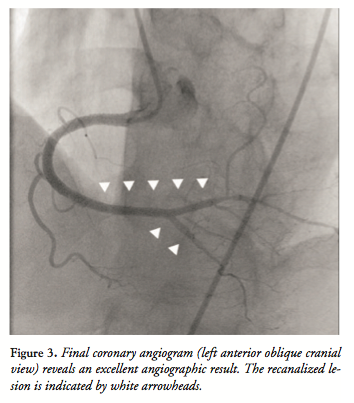

advanced into the bifurcation lesion antegrade, and a 1.75 x 15 mm Sapphire balloon (Orbusneich Medical) was advanced retrograde. The bidirectional kissing-balloon technique was then performed (Figure 2F). Following this, we successfully navigated a Balance guidewire (Abbott Vascular) antegrade into the PAV with a Crusade. Subsequently, we performed antegrade kissing-balloon angioplasty with a 2.0 x 15 mm Sapphire balloon in the PDA and a 1.75 x 15 mm Sapphire balloon in the PAV (Figure 2G). A 2.25 x 23 mm Xience Prime stent was deployed from the middle segment of the RCA to the PAV (Figure 2H). Postdilatation was performed with stent balloons, and a final coronary angiogram revealed an excellent result, with preserved flow in both the PAV and PDA (Figure 3). The postprocedure course was uneventful, and no major complications, including severe ischemic events, heart failure, or access-site complications, were observed. The patient was discharged 2 days after the procedure without symptoms.